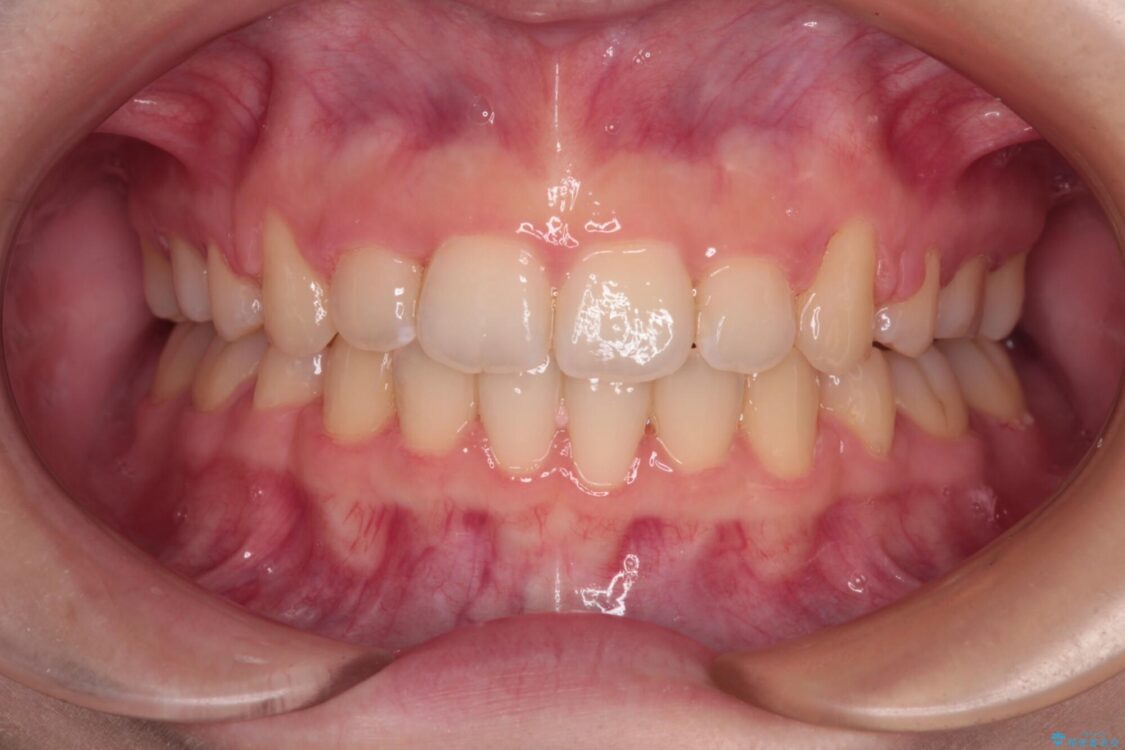

治療後

• 【モニター】口が閉じられない ワイヤー装置での抜歯矯正 治療後画像

治療後について

舌の突出癖があり、前歯の移動量も多くなるため、治療期間は長くなると予想されましたが、13ヶ月という予定の半分程度の期間で終えることができました。